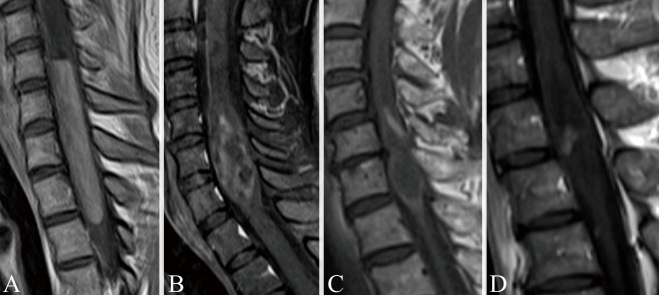

Spinal ependymomas are common intramedullary tumors that can show dynamic changes in magnetic resonance imaging findings over time. This study aimed to analyze these imaging changes and their implications for perioperative management. The retrospective study included patients diagnosed with World Health Organization grade 2 spinal ependymoma who underwent surgical resection and had at least 2 preoperative magnetic resonance imaging scans. Patients were divided into 2 groups based on the presence or absence of radiographic changes on magnetic resonance imaging. Magnetic resonance imaging analyses included non-contrast T1- and T2-weighted images, as well as gadolinium-enhanced T1-weighted images when available. Key features evaluated included intraparenchymal edema, hemosiderin deposition, syringomyelia, and cyst components. Changes in tumor size and contrast enhancement patterns were documented. Radiographic changes were identified in 4 out of 15 cases (26.7%). All cases with imaging changes exhibited hemosiderin deposition or hemorrhage, significantly higher than in cases without changes (100% vs. 18.2%, p < 0.05). No significant differences were observed in the presence of cystic components, syringomyelia, or edema between the groups. In the group with radiographic changes, the timeframe for these changes in the images ranged from 3 days to several years. Spinal ependymomas can demonstrate dynamic magnetic resonance imaging changes during the preoperative period, including both growth and reduction in tumor size. The presence of hemosiderin deposition or hemorrhage might be associated with these imaging changes. Proper timing of magnetic resonance imaging is crucial for informing surgical planning and optimizing treatment strategies for patients with spinal ependymomas.

Abstract Image